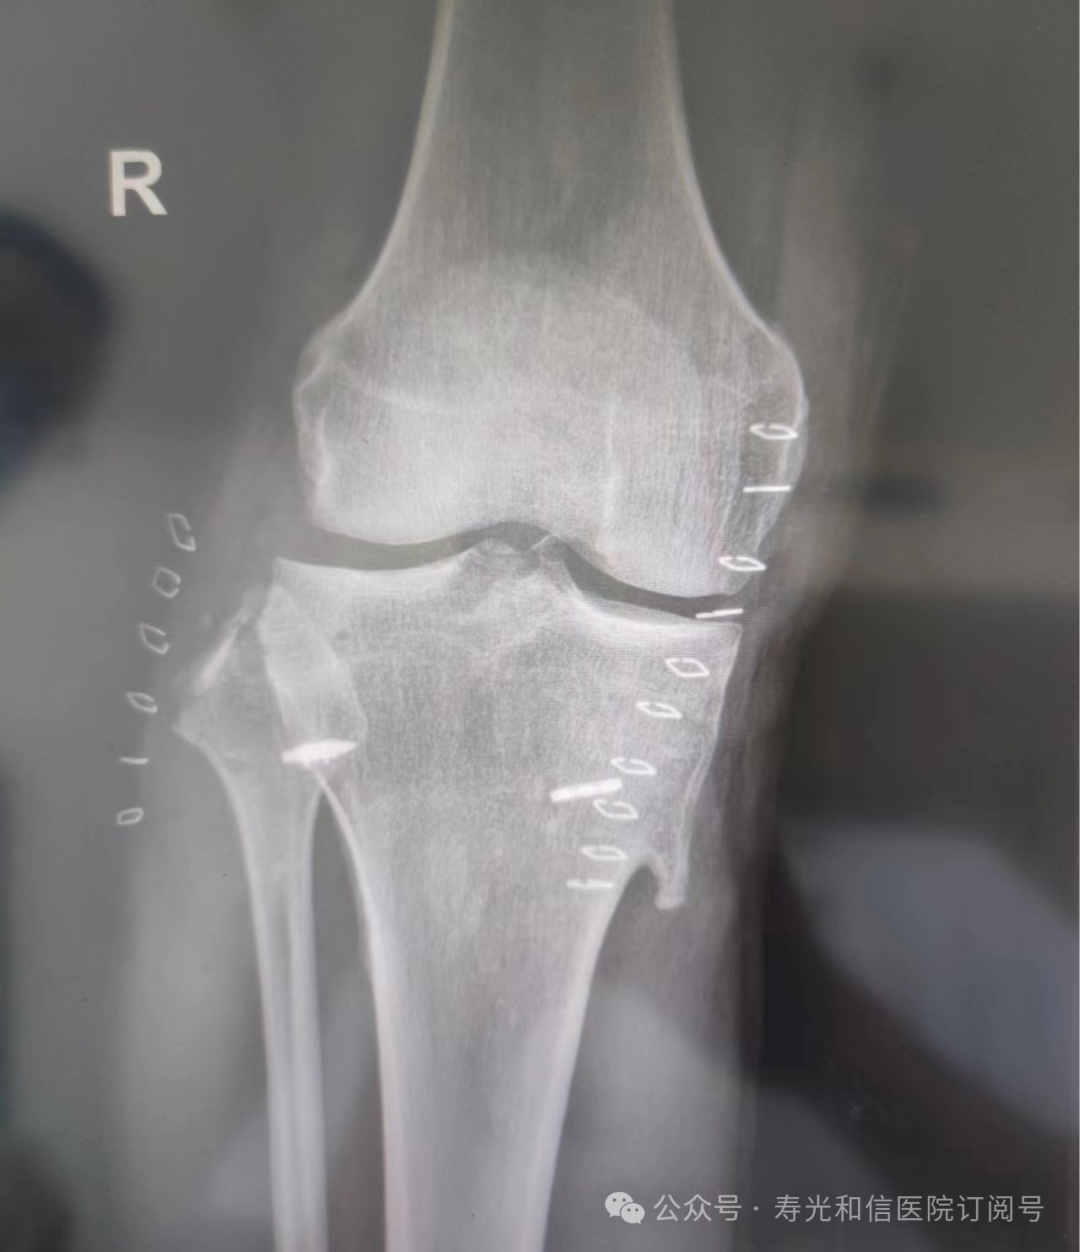

患者经120接诊,完善相关辅助检查后收入寿光和信医院骨外科。检查发现,患者右锁骨骨折、左股骨颈骨折、左大转子撕脱骨折、右膝关节前交叉韧带止点撕脱骨折、右膝关节外侧副韧带损伤、颅骨骨折及全身多处皮肤挫伤。因患者是外地来寿人员,家属短时间内不能赶过来,并且患者家庭经济条件较差,没有缴纳住院手术费的能力。但是股骨颈骨折后,股骨头坏死发生几率较高,手术越早进行,越有利于减少发生股骨头坏死的几率。骨外科主任李刚始终牢记救死扶伤的神圣职责,本着为病人负责的原则,坚定地选择先行为患者实行手术治疗。

与患者本人充分沟通后,李刚主任率领骨外科团队,经过充分的术前讨论及术前准备,于2024年9月1日为患者在全身麻醉下实施了4个半小时的内固定手术治疗。“时间就是生命”,手术过程中,全体参与人员密切观察病情变化,敏锐发现早期异常指标,争分夺秒,一丝不苟地做好各项抢救救治工作,做到瞬间判断、正确评估、果断处理,赢得了抢救患者的“黄金时机”,确保了手术的顺利完成。

在为其进行股骨颈骨折治疗时,手术团队为其采取了股骨颈动力交叉钉系统,这是一种新型股骨颈内固定系统,属微创植入,较从前的技术具有手术时间短、创伤小、力学稳定、滑动加压等优点。同时,患者恢复快,可早期离床、不负重下活动,缩短住院时间及康复时间,有效降低患者股骨颈骨折不愈合发生率,降低长期卧床合并症和死亡率。